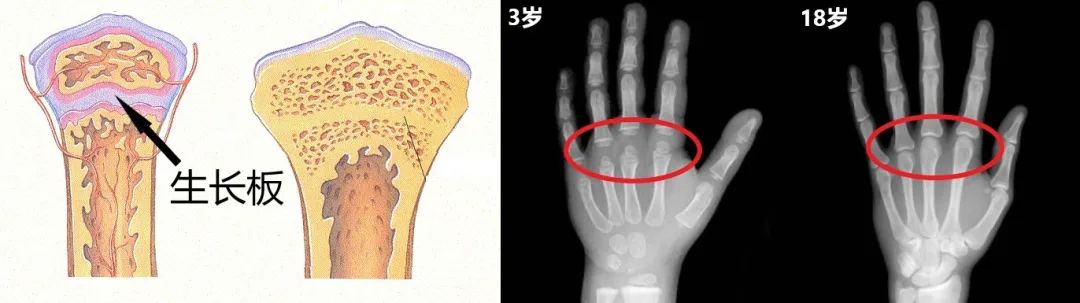

栄養・生化学辞典 骨端成長板の用語解説 骨端部成長板,骨端板,骨端軟骨ともいう.長骨の先端部分にあって骨が成長している部分.板状の組織を形成していることからいう.栄養・生化学辞典 骨端成長板の用語解説 骨端部成長板,骨端板,骨端軟骨ともいう.長骨の先端部分にあって骨が成長している部分.板状の組織を形成していることからいう.近年來,利用生長板調控手術的原理,在生長板兩側植入生長板抑制骨板,達到生長抑制(growth inhibition)或減緩(growth tethering)的目的,等到矯正完成之後,再把內置之生長板抑制骨板拿掉即可恢復正常成長。 因為手術本身並不會破壞生長板,所以可以在較

骨の成長を理解するには、長管骨で考えると分かり易いので、次に長管骨の構造を見てみましょう。 長管骨の構造 長管骨は下の図(イラスト)のように、 海綿骨(梁状の網目構造の骨) 皮質骨(硬くて緻密な骨) 成長軟骨板(成長過程の子供の場合栄養・生化学辞典 骨端成長板の用語解説 骨端部成長板,骨端板,骨端軟骨ともいう.長骨の先端部分にあって骨が成長している部分.板状の組織を形成していることからいう.骨齡不等於實際年齡!想增高? 請掌握3大關鍵期 記者記者蔣文宜/台北報導 暑假一過,許多青春期的孩子像吹氣球般,突然就長高好幾公分,如果發現自己的孩子明顯被同學追趕過去,家長可能會開始擔憂,深怕自己的孩子以後會不會長不高?

骨知識 孩子成長密碼 察看生長板

康程中醫診所 生長板 骨骺線 閉合 是骨骼正常發育的一個過程 骨骺與乾骺端之間的軟骨 在小朋友的手部x光片上表現為 Facebook